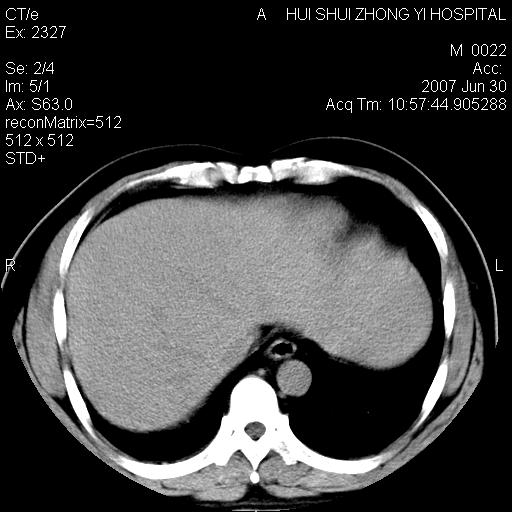

男,44岁,体检。

肝右叶密度减低区?

支持双肾结石,肝右叶低密度影为胆囊部分容积效应。

肝右叶低密度影为胆囊部分容积效应?为什么s43.0层面下来不见胆囊影,而是相隔了一层才见胆囊影。这是按我们扫描的顺序发的,但是是追加扫描的。

支持双肾结石,肝右叶低密度影为胆囊部分容积效应

病人呼吸动了,第四层应该在第五\\六层之间。肝右叶低密度影为胆囊部分容积效应。双肾结石。

双肾结石,肝右叶低密度影为胆囊部分容积效应。